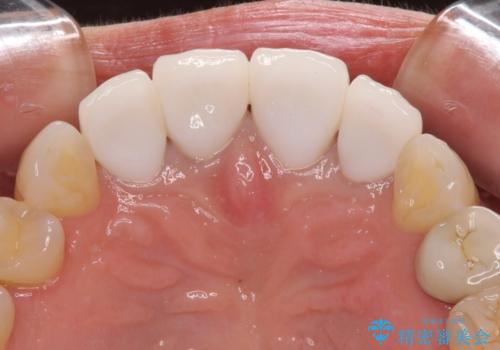

左右対称で明るく自然な前歯に仕上げることができました。